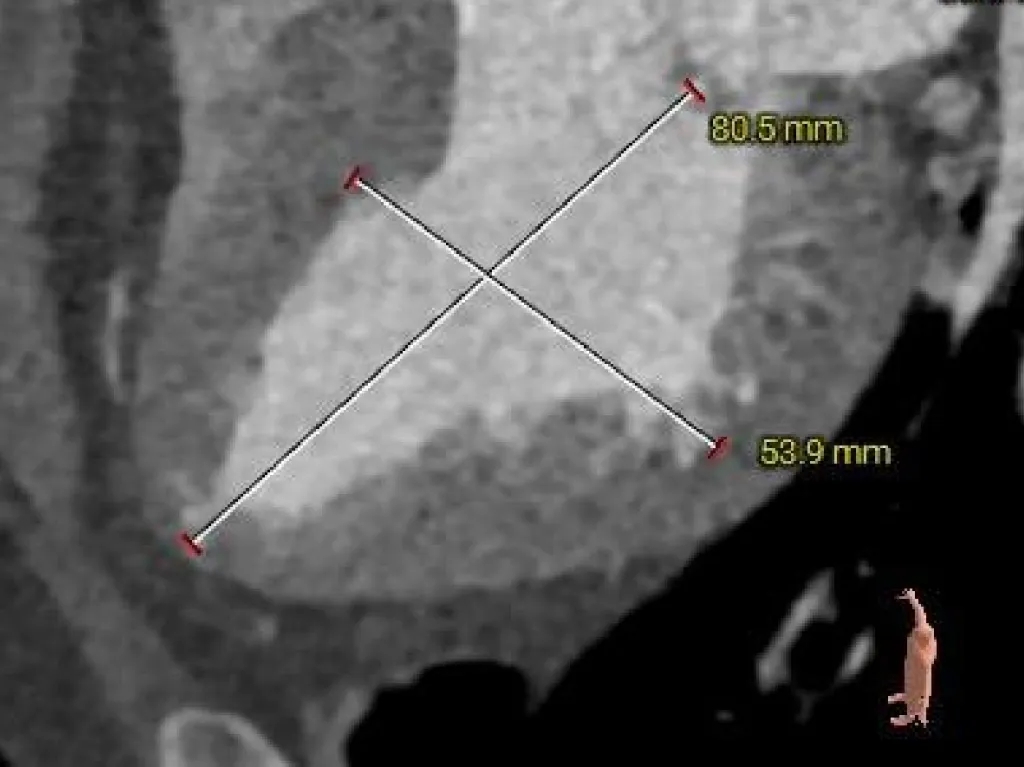

左室测量

-

收缩期心室偏大

心室壁厚度尚可

外周入路评估

外周无明显迂曲、钙化;血管内径可

62°横位心